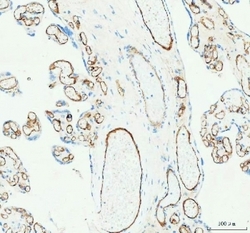

- Submitted by

- NSJ Bioreagents (provider)

- Main image

- Experimental details

- IHC staining of FFPE human placental tissue with CD31 antibody. HIER: boil tissue sections in pH8 EDTA for 20 min and allow to cool before testing.